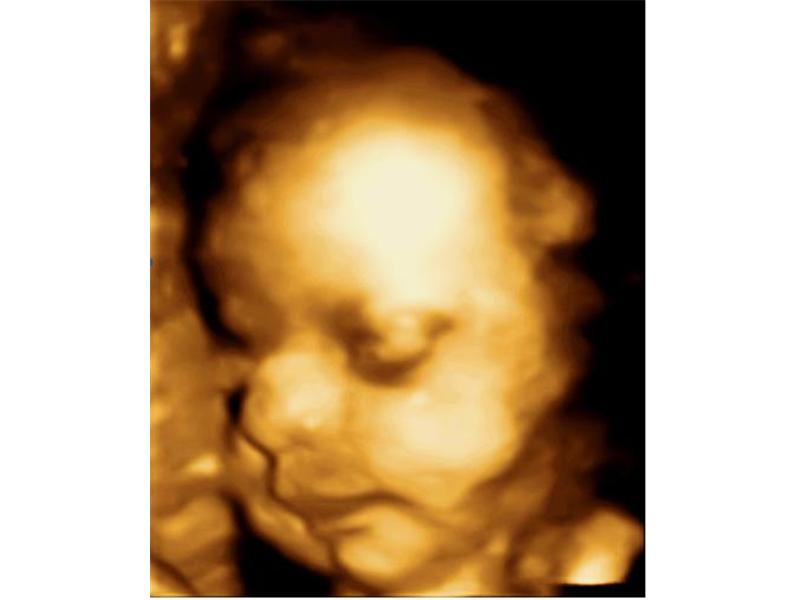

Zdroj: archiv redakce